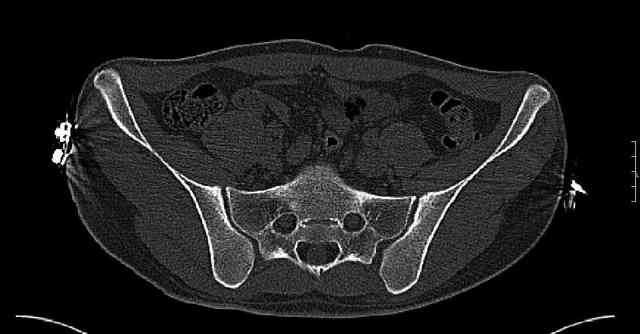

Some more images. Does it help to guess which part of the acetabulum is displaced?